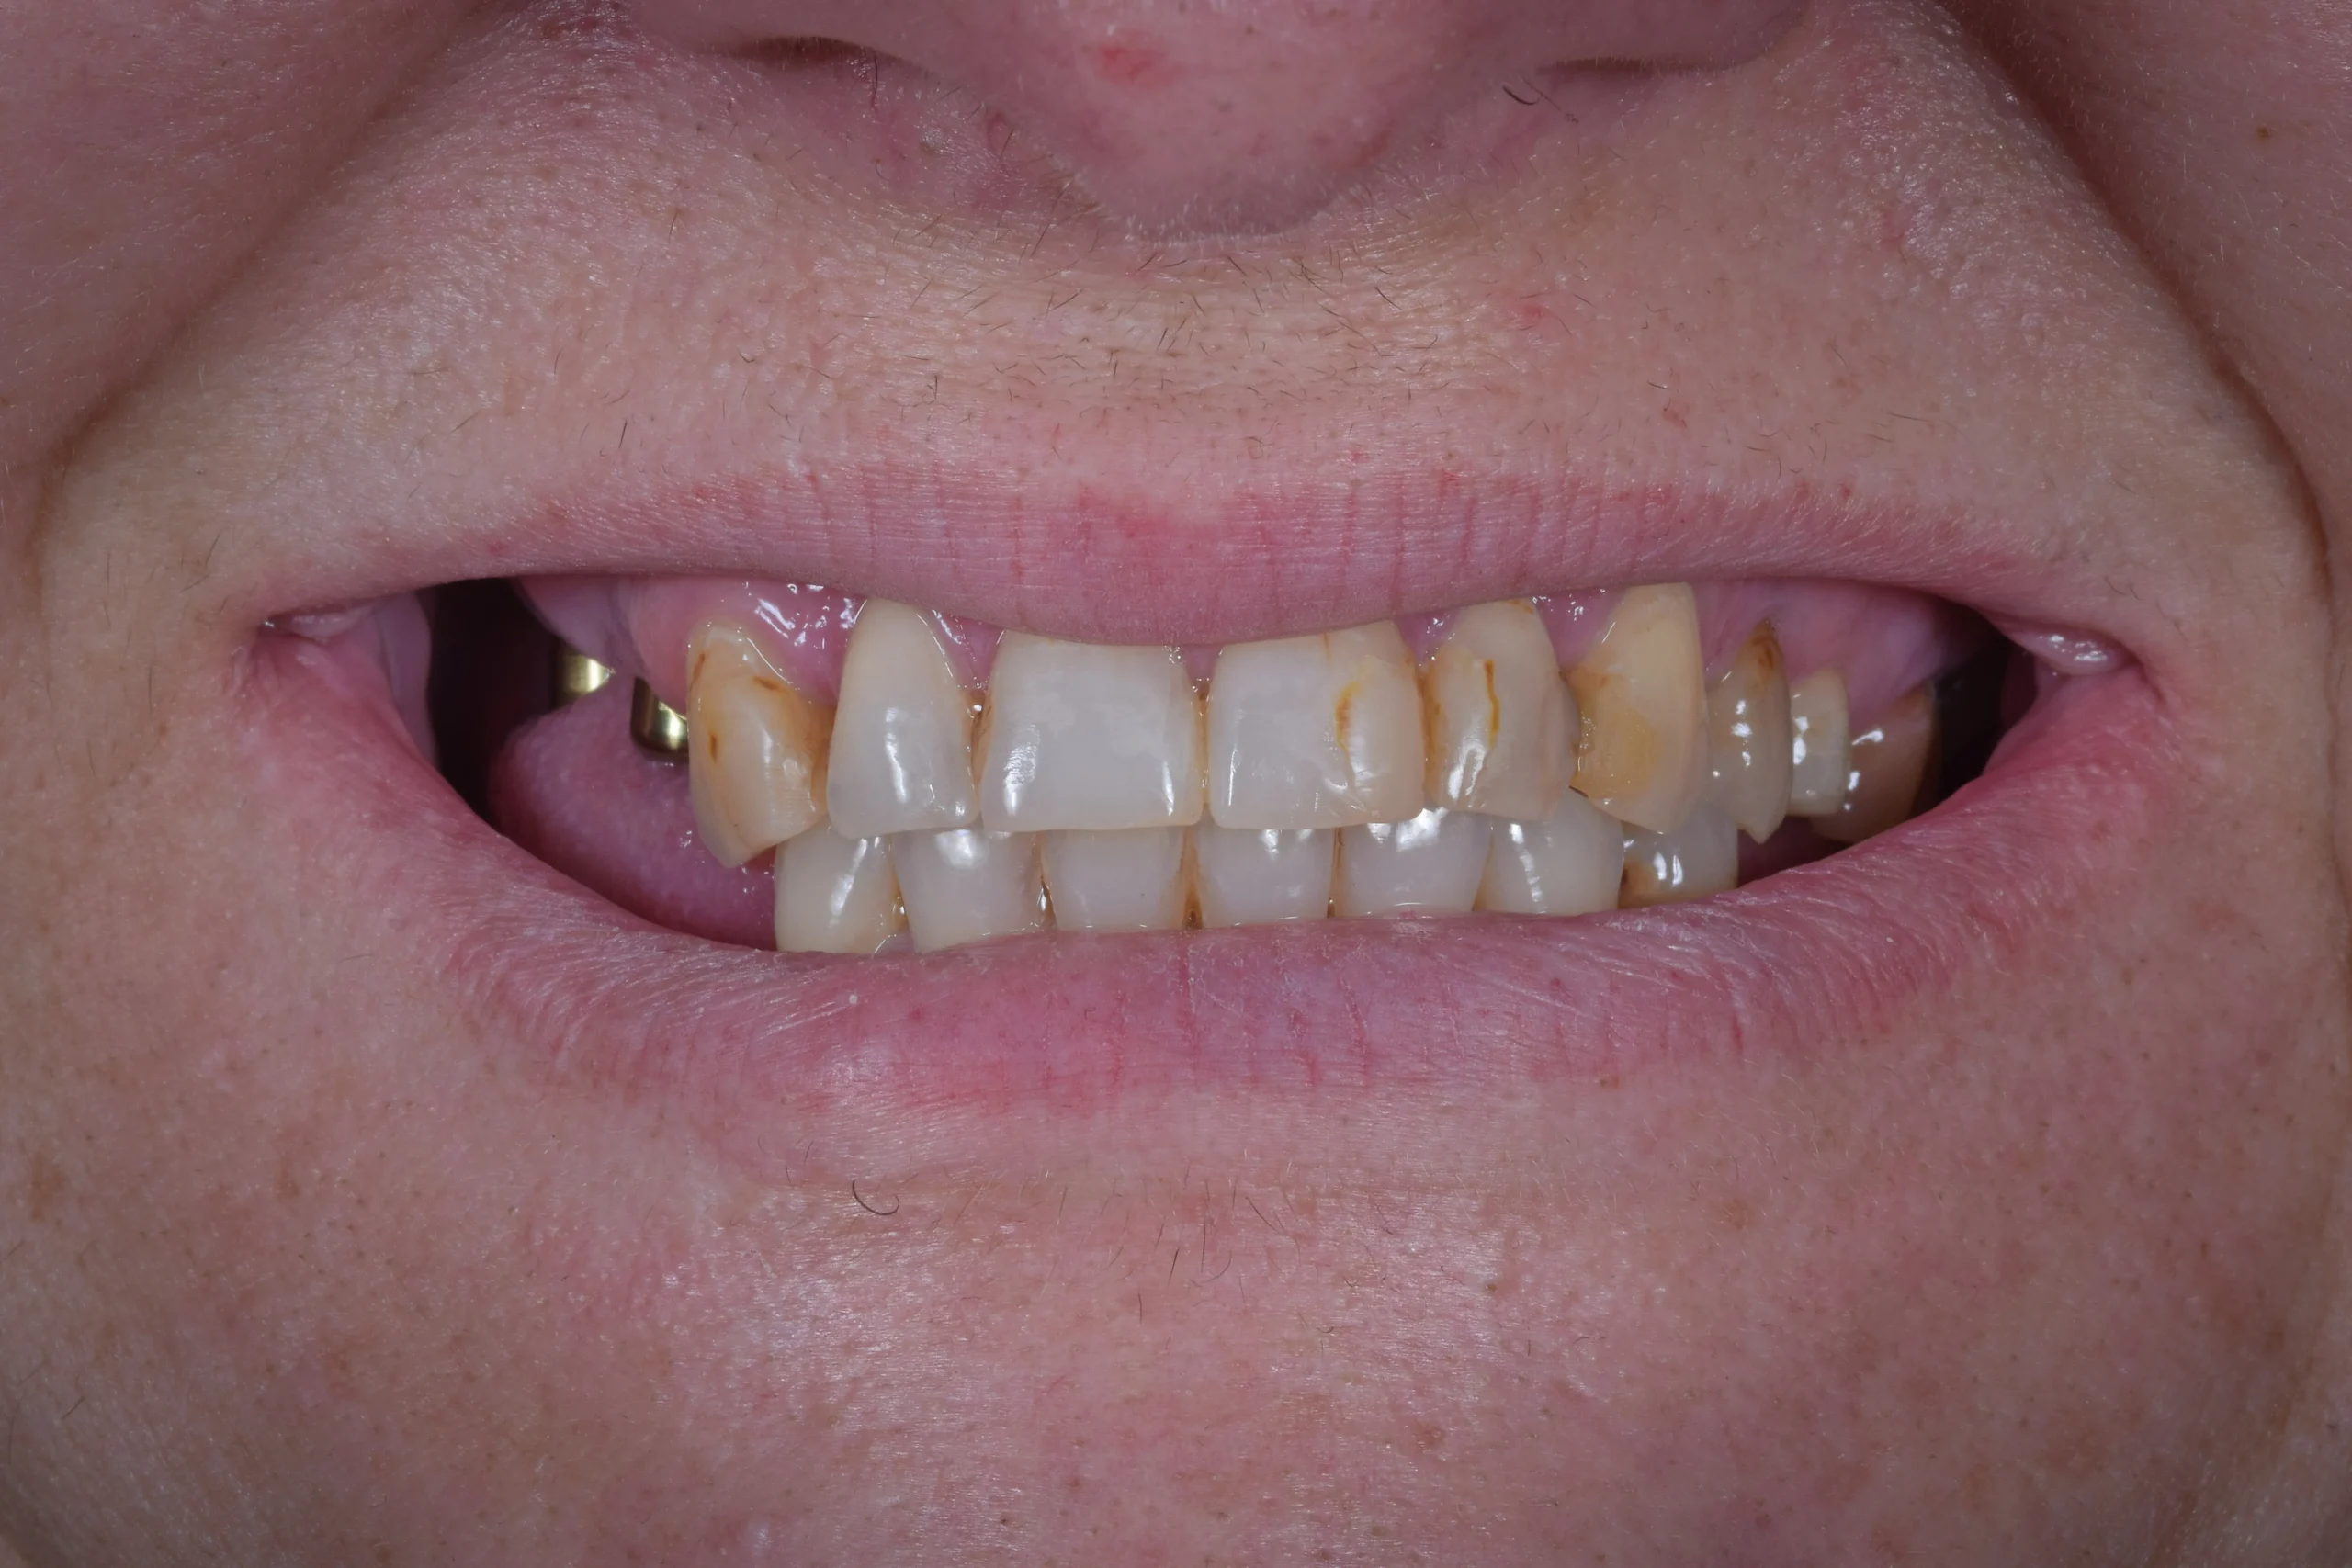

This patient came to our clinic from Bulgaria. She had a severe fear of dentists, multiple lost teeth in both jaws and an uneven bite because of that.

After the examination and the analysis, the therapy plan was full mouth reconstruction with dental implants and zirconia crowns and bridges. The remaining roots were extracted and six dental implants were placed using a surgical guide and digital workflow.